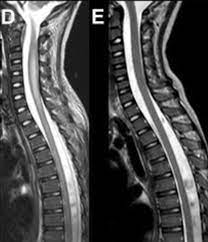

Jan 14, 2017 · transverse myelitis is an inflammatory condition of the spinal cord associated with rapidly progressive neurologic dysfunction.

In the acute setting, there is often associated contrast enhancement. G37.3 acute transverse myelitis in demyelinating disease of central nervous system g37.4 subacute necrotizing myelitis of central nervous system g37.5 concentric sclerosis balo of central nervous system g37.8 other specified demyelinating diseases of central nervous system g37.9 demyelinating disease of central nervous system, unspecified They most commonly affect elderly men and are classically found in the thoracolumbar region. Transverse myelitis postsurgical spine avm brachial plexus post radiation therapy, eval for mass lesions, entrapment, denervation cervical spine w and w/o contrast 72156 thoracic disc disease pain radiculopathy trauma thoracic spine w/o contrast 72146 tumor infection ms syrinx transverse myelitis postsurgical spine avm Compression of the upper spinal cord, multiple sclerosis, transverse myelitis, behçet's disease, osteogenesis imperfecta lhermitte phenomenon , also called the barber chair phenomenon , is an uncomfortable electrical sensation that runs through the back and into the limbs. Jan 14, 2017 · transverse myelitis is an inflammatory condition of the spinal cord associated with rapidly progressive neurologic dysfunction. As part of a health sciences university, baylor medicine in houston, texas puts the latest treatments, innovations, and therapies in the hands of its highly trained doctors and care teams, who are working together to develop and deliver a care plan personalized for you. Rare neurological complications include transverse myelitis and/or cauda equina syndrome 20, 21; The av shunt is located inside the dura mater close to the spinal nerve root where the arterial blood from a.